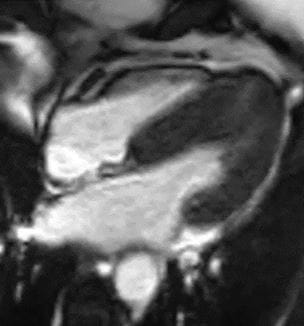

UH Team First to Report Using Cardiac MRI for LAAC Pre-procedure Planning

Approach is a solution for the current contrast media shortage, as well as other scenarios - Innovations in Cardiovascular Medicine & Surgery | Summer 2022